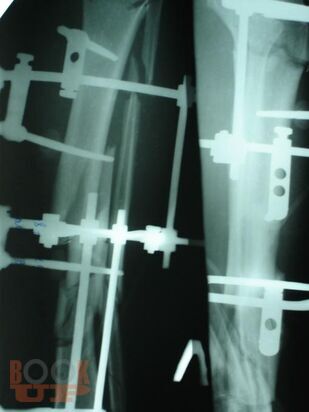

Учебно-методическое пособие содержит необходимую информацию для врачей по вопросам оказания специализированной помощи пострадавшим с тяжелой травмой костей нижних конечностей. Подробно освещены вопросы тактики оказания специализированной и высококвалифицированной помощи пострадавшим с тяжелыми монолокальными, множественными и сочетанными переломами костей конечностей в зависимости от периода развития травматической болезни. Отмечено, что в настоящее время оперативное лечение является основным при лечении переломов костей конечностей с учетом хирургической тактики контроля повреждения. Особое внимание уделено профилактике и лечению ранних осложнений тяжелых повреждений опорно-двигательного аппарата – синдрому жировой эмболии, тромбоэмболическим осложнениям. В пособии обобщен более, чем 20- летний опыт лечения пациентов с тяжелой травмой костей конечностей.